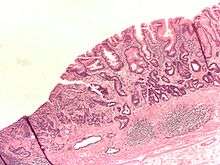

- Gastric adenocarcinoma is a malignant epithelial tumour, originating from glandular epithelium of the gastric mucosa. Stomach cancers are overwhelmingly adenocarcinomas (90%).[51] Histologically, there are two major types of gastric adenocarcinoma (Lauren classification): intestinal type or diffuse type. Adenocarcinomas tend to aggressively invade the gastric wall, infiltrating the muscularis mucosae, the submucosa and thence the muscularis propria. Intestinal type adenocarcinoma tumour cells describe irregular tubular structures, harbouring pluristratification, multiple lumens, reduced stroma ("back to back" aspect). Often, it associates intestinal metaplasia in neighbouring mucosa. Depending on glandular architecture, cellular pleomorphism and mucosecretion, adenocarcinoma may present 3 degrees of differentiation: well, moderate and poorly differentiated. Diffuse type adenocarcinoma (mucinous, colloid, linitis plastica, leather-bottle stomach) tumour cells are discohesive and secrete mucus, which is delivered in the interstitium, producing large pools of mucus/colloid (optically "empty" spaces). It is poorly differentiated. If the mucus remains inside the tumour cell, it pushes the nucleus to the periphery: "signet-ring cell".